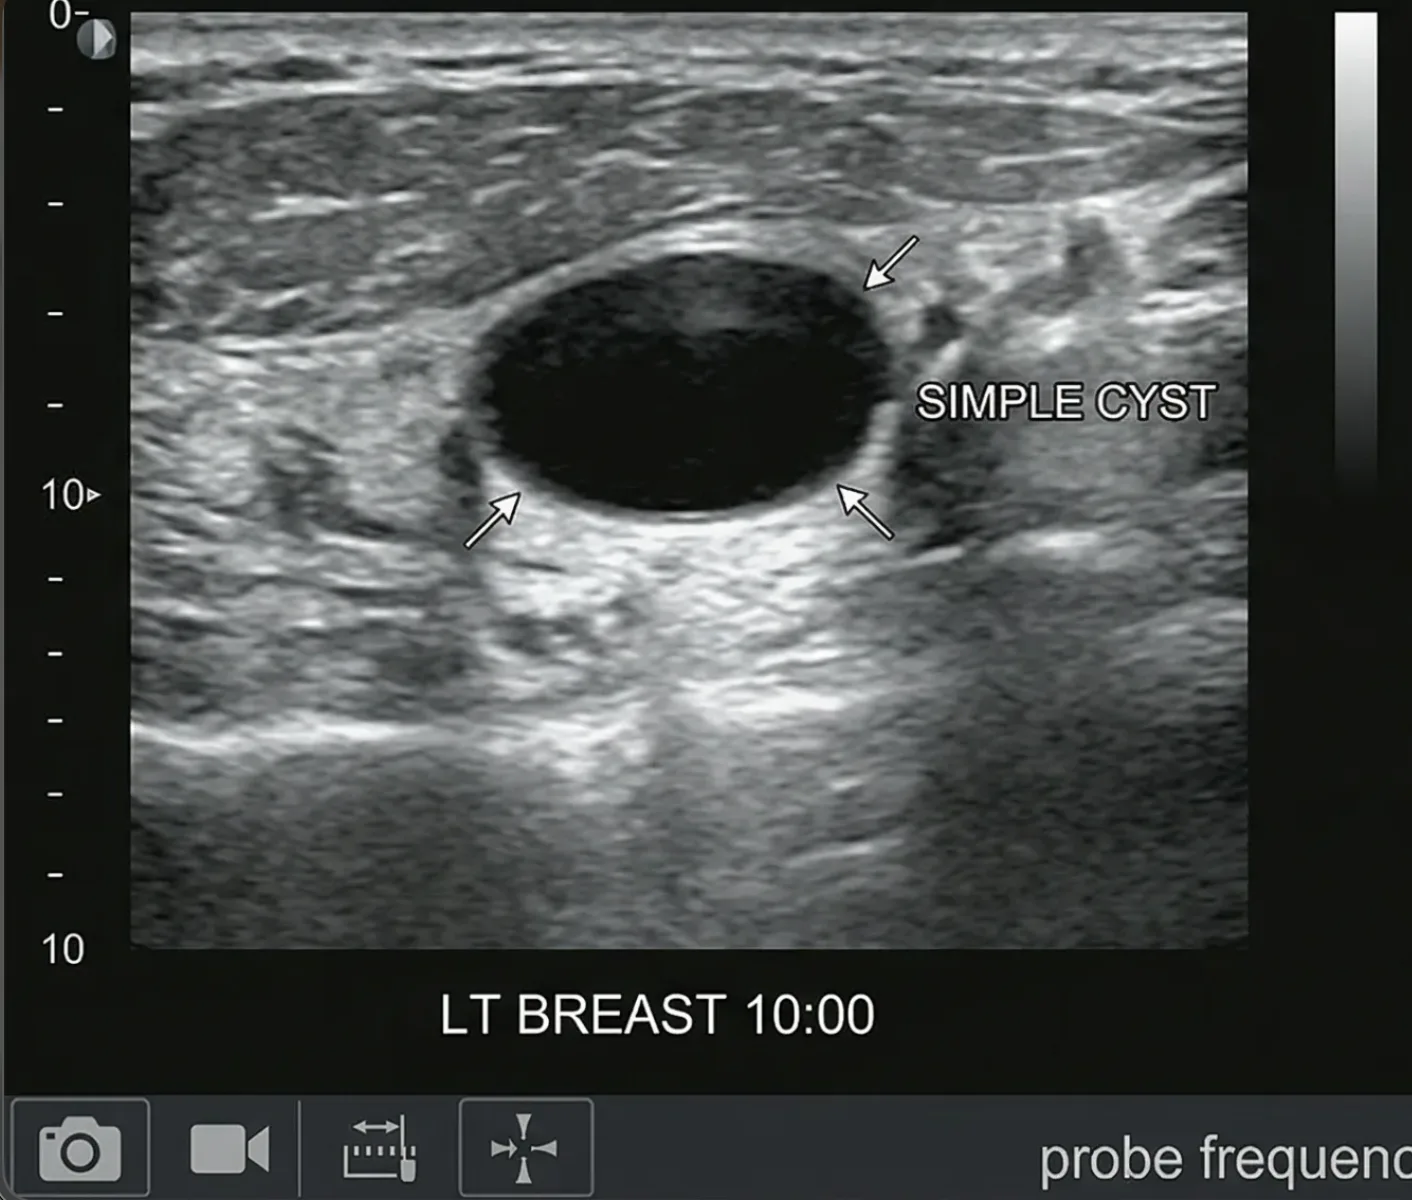

Are all cysts cancerous?

No, the majority of cysts are benign (non-cancerous). Many cysts are common and harmless, especially ovarian cysts or simple cysts seen on imaging. However, imaging tests and medical evaluation are important to determine the nature of the cyst and whether any follow-up is needed.